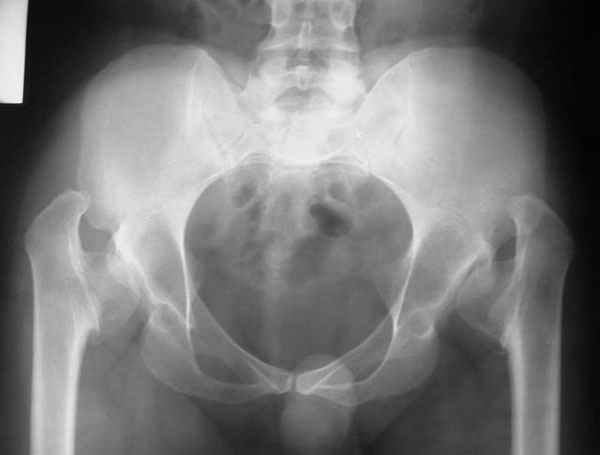

It appears that this patient has bilateral congenital hip displasia, as presented on the radiographs. As shown, the problem involves both sides of the hip joint: the acetabulum and proximal femur.

This patient is noted to have a very vertical joint surface orientation, as well, with retroversion of the acetabulum.

In a hip with normal version, (on discussion list) Hip Pain (Dr.Kullerkann) the lines connecting the anterior and posterior acetabular wall as seen on an AP radiograph usually intersect at one point near the superior and lateral portion of the acetabulum. As an example of an abnormal hip, a patient with a retroverted acetabulum will show the figure 8 pattern, with the two shadows crossing over the femoral head. In this particular patient, again it appears that there is a significant amount of retroversion of the acetabular wall, as the anterior wall appears to be more anteriorly displaced than in a normal hip.

In this patient, it appears that addressing either the femur or the acetabulum will be insufficient to help correct this patient’s problem. It would be necessary to approach both sides of the hip joint to correct the hip dysplasia.

The pre-operative planning would need to be done with the use of more radiographs for assessment of the hip dysplasia. These x-rays include a repeat AP pelvis, separate AP and lateral of the hips, long-standing femoral axis views of both legs, false profile view, as well as abduction and adduction films.

Pic. 1-5 preop plan; 6-8 similar case